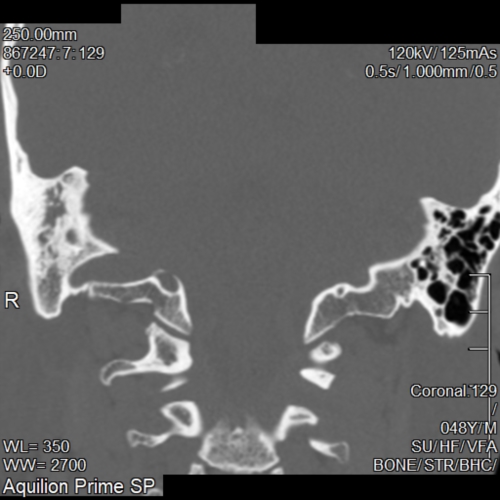

The CT scan report came back saying I had Chronic Otomastoiditus and showed opacification of the Mastoid bone and middle ear space. (See pictures)

I think I can see thickening of the of the right ear drum. But I'm not 100% sure. Maybe any curious radiologists out there can correct me. The right middle ear space is opacified so I find it difficult to see any obvious changes to the ossicular chain.